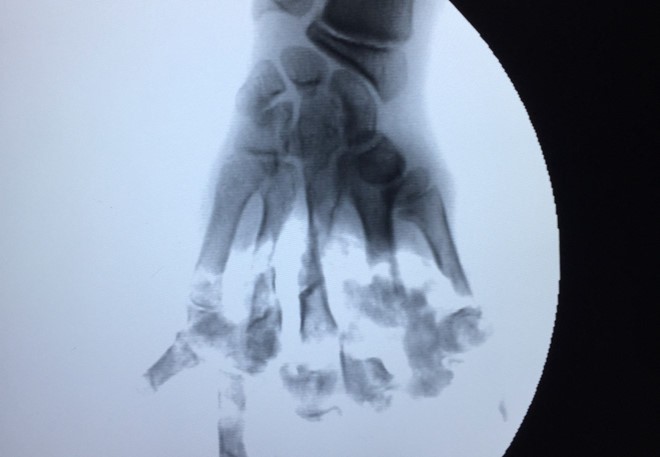

Hình ảnh phim chụp bàn tay của nạn nhân. Ảnh: Tùng Chi.

Qua chụp X-quang, cho thấy hình ảnh các đốt xương 5 ngón tay bị nghiền nát, cụt hết xương bàn ngón. Bệnh nhân được chỉ định cắt lọc tạo mỏm cụt 1/2 bàn tay và tiêm thuốc giảm đau.